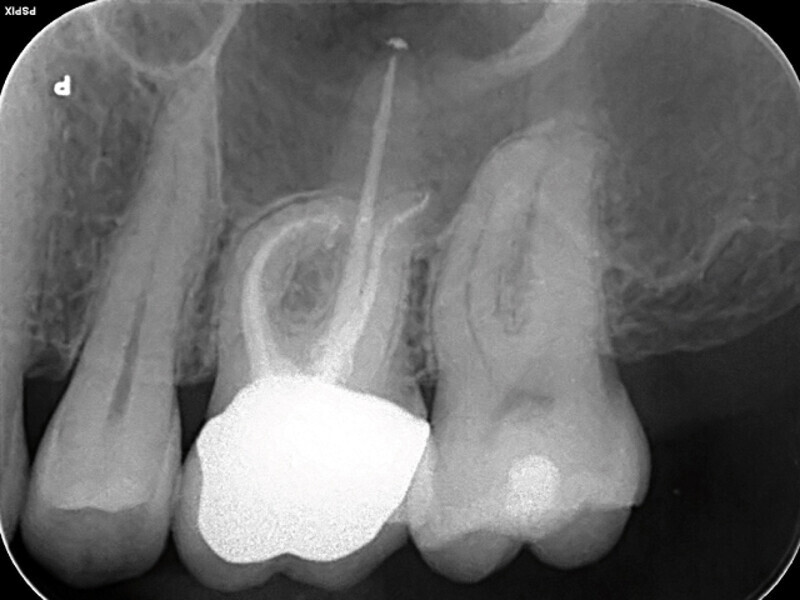

Endodontické ošetření – případová studie